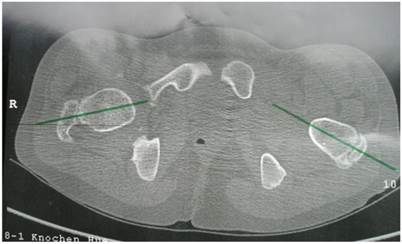

Group 2: Patients showed excessive femoral anteversion of the hips secondary to significant acetabulo-femoral dysplasia (IR-internal rotation: 90 degrees, ER-external rotation: 30 degrees). We measured the torsion of the femur by means of CT scan. There was femoral anteversion of right hip of 38° and of the left hip of 45 ° respectively in a 13-year-old-boy (fig 4). CT scan to measure the rotation of the knees showed internal rotation 7° of the right knee and 20° rotation of the left knee in connection with trochlear dysplasia (fig 5).

Fig 5

Axial CT scan of the knees showed internal rotation 7° of the right knee and 20° rotation of the left knee, note the epiphyseal fragmentations associated with trochlear dysplasia.